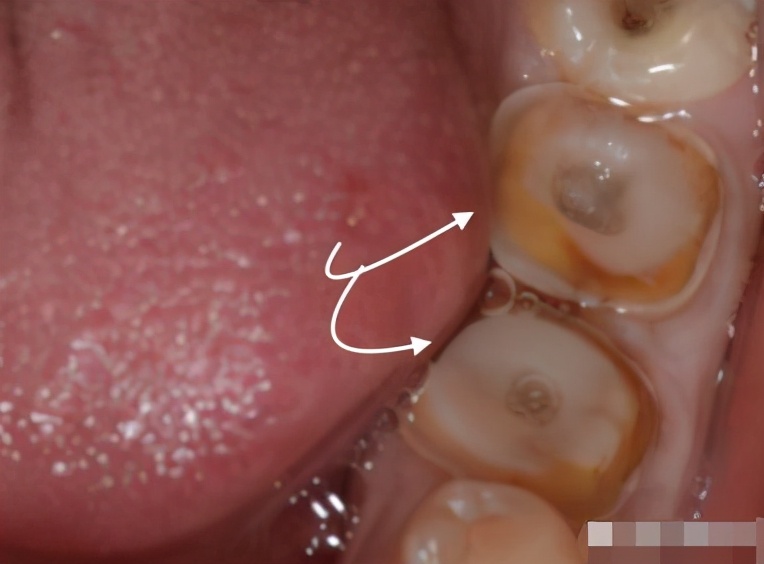

5、无充足的牙齿结构支撑牙冠

如果牙齿的高度、体积不充足则有可能无法很结实地固定住要安装的牙冠,那么牙冠就容易发生脱落,这种情况尤其常见于后牙。